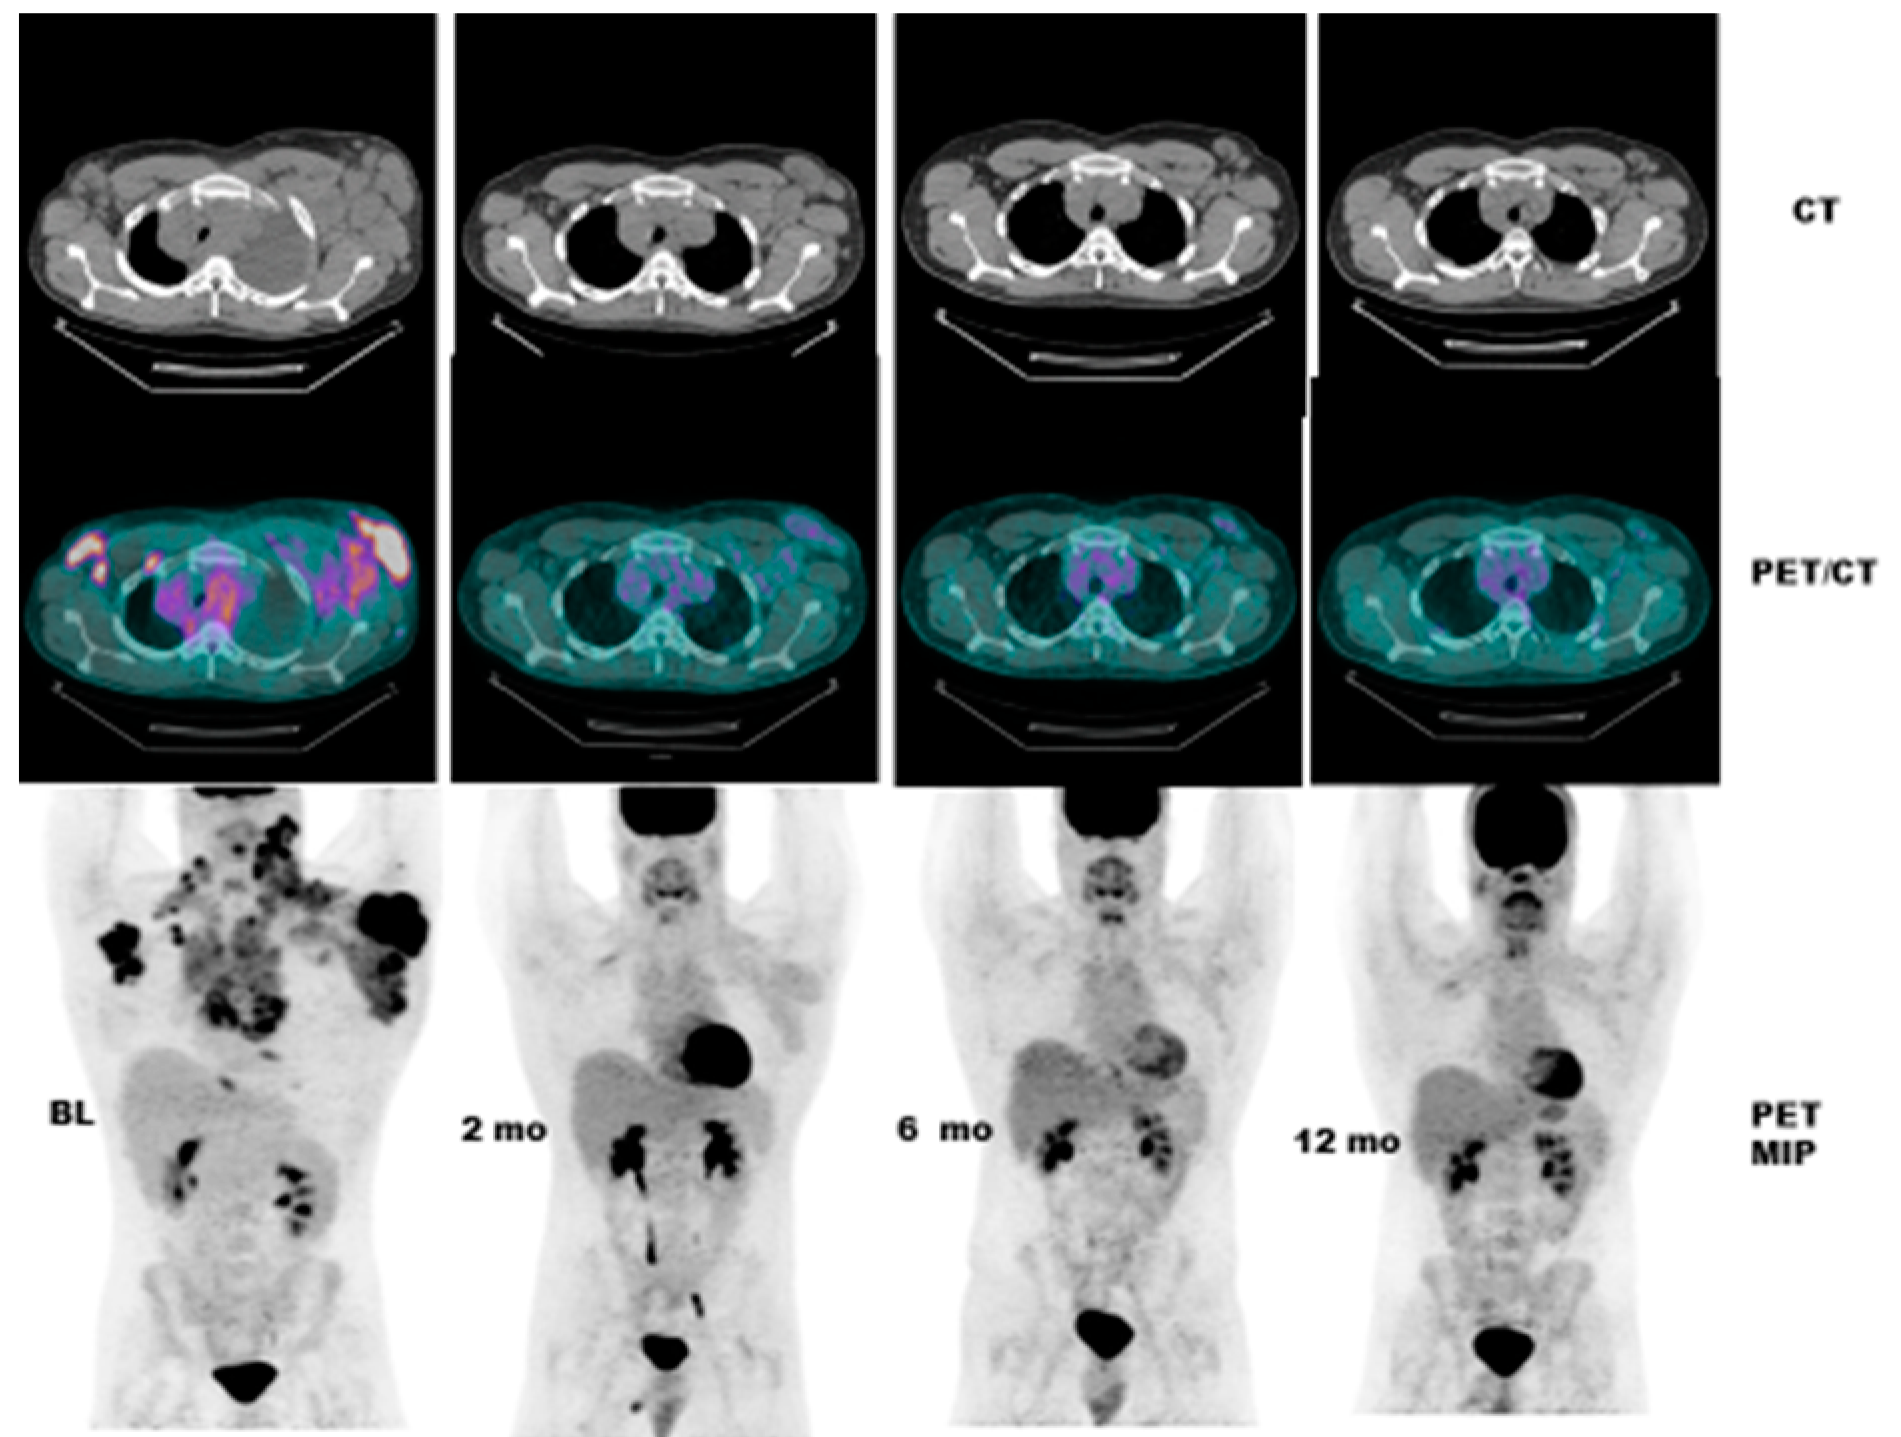

- Case # 4:

- This is a 22 y/o male with Hodgkin lymphoma (nodular sclerosis type). He had complete metabolic response after 2 cycles of chemotherapy (ABVD) but only partial anatomic response. He completed 6 cycles of therapy with complete metabolic response but residual anatomic abnormalities. He had consolidation radiation therapy, about 1 month after completing chemotherapy; about 2 months after completing radiation therapy, there was no change. It is not uncommon to have residual masses after therapy for lymphoma, especially Hodgkin lymphoma, that may complicate anatomic response assessment [35,40,41,42] (Figure 5).